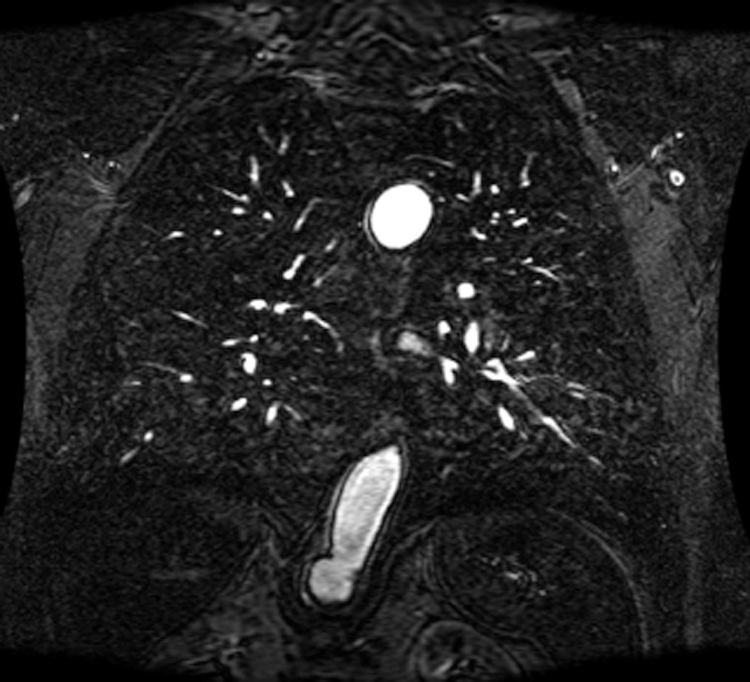

An intelligent-MRI VLC has been implemented for MRI image transmission using VLC and RF interference is eliminated. The proposed intelligent-MRI VLC system is experimentally analyzed using MRI images of different sizes i.e., 100, 115, and 120 KB respectively. These MRI images of the chest are downloaded from a medical database physionet.org. The downloaded MRI images are of T1 weighted type, which has grey matter darker than white matter was used for the proposed work. Images are acquired using Image Acquisition (IMAQ) in LabVIEW and transmitted using visible light in an indoor environment. The downloaded MRI images of various sizes are shown in Figs. 13–15.

Figure 13: 100 KB MRI image